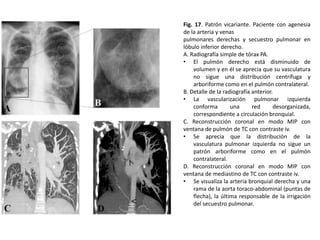

Patrón de vascularización vicariante

• Consiste en la visualización de la circulación

arterial bronquial en la radiografía simple de

tórax, que en condiciones normales no se

identifica.

• Cuando las arterias bronquiales se hacen

patentes en los campos pulmonares se perciben

como una red anárquica de líneas en

contraposición a la disposición normal de los

vasos pulmonares, que sigue una distribución

arboriforme

Las causas de patrón vicariante son todas aquellas que disminuyan de manera importante el

aflujo de sangre a los pulmones a través de las arterias pulmonares provocando que las

arterias bronquiales funcionen como colaterales causando su dilatación

Fig. 17. Patrón vicariante. Paciente con agenesia

de la arteria y venas

pulmonares derechas y secuestro pulmonar en

lóbulo inferior derecho.

A. Radiografía simple de tórax PA.

• El pulmón derecho está disminuido de

volumen y en él se aprecia que su vasculatura

no sigue una distribución centrífuga y

arboriforme como en el pulmón contralateral.

B. Detalle de la radiografía anterior.

• La vascularización pulmonar izquierda

conforma

una

red

desorganizada,

correspondiente a circulación bronquial.

C. Reconstrucción coronal en modo MIP con

ventana de pulmón de TC con contraste iv.

• Se aprecia que la distribución de la

vasculatura pulmonar izquierda no sigue un

patrón arboriforme como en el pulmón

contralateral.

D. Reconstrucción coronal en modo MIP con

ventana de mediastino de TC con contraste iv.

• Se visualiza la arteria bronquial derecha y una

rama de la aorta toraco-abdominal (puntas de

flecha), la última responsable de la irrigación

del secuestro pulmonar.